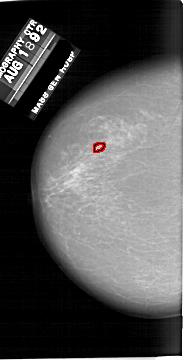

FILE: A_1649_1.LEFT_CC.OVERLAY

TOTAL_ABNORMALITIES 1

ABNORMALITY 1

LESION_TYPE CALCIFICATION TYPE PLEOMORPHIC DISTRIBUTION CLUSTERED

ASSESSMENT 4

SUBTLETY 4

PATHOLOGY BENIGN

TOTAL_OUTLINES 1